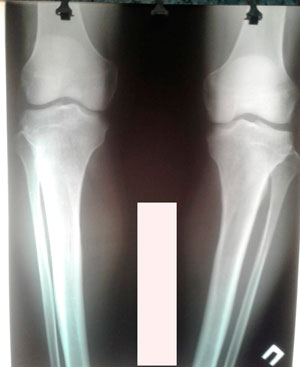

Дата операции - 18.06.2019г.

Дата снятия аппаратов - 20.09.2019.

Срок сращения - 93 дня.